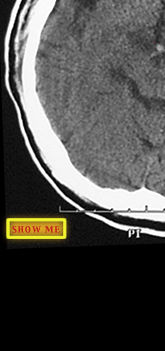

Find the thrombus.